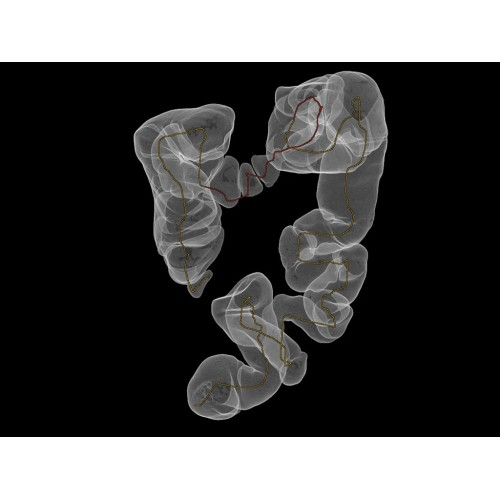

Компьютерный томограф GE Brivo CT385 представляет собой современное диагностическое оборудование, сочетающее высокую точность исследований с повышенным комфортом для пациентов. Этот аппарат открывает новые возможности для детальной визуализации анатомических структур.

Позволяет проводить комплексные исследования всех анатомических зон, включая нейровизуализацию, ангиографию, исследования органов грудной и брюшной полости. Особенно эффективен для раннего выявления онкологических заболеваний.

Обеспечивает высокую точность при кардиологических исследованиях, визуализации костных структур и суставов. Подходит для динамического наблюдения в ходе лечения.